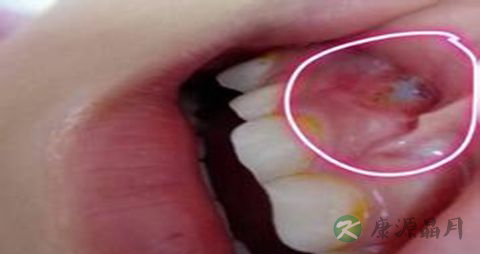

炎症性的牙龈萎缩,主要表现为牙龈红肿胀痛,刷牙时常见出血。而老年牙龈萎缩常使裸露了的牙极对冷热的温度变化及酸性食物等异常敏感,妨碍进食,降低生活质量,尢应注意防治。

2、防治炎性口腔病。牙周炎、牙结石、口腔溃疡、牙龈炎、牙龈脓肿、食物嵌塞及不大合适的假牙等,都是刺激引致牙龈萎缩的原因,所以应定期到医院检查治疗,并进行有关口腔自我保健知识的咨询;对于已经萎缩的牙龈,也可以手术治疗。